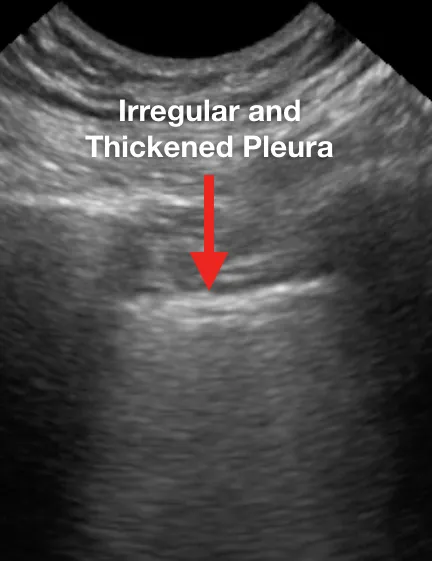

Ниже представлен ряд изображений патологических изменений, которые Вы можете увидеть при УЗИ легких пациентов с COVID-19. Эти изменения можно найти в любой части легкого, поскольку COVID-19 имеет мультифокальное распределение. Возможно сочетание областей нормального легкого и области с патологией. Патологические изменения легких могут отсутствовать в начале заболевания и при легком течении COVID-19, однако, по мере его прогрессирования, Вы можете наблюдать всё больше патологических изменений.

Ниже приведены примеры УЗ-картины легких пациентов с COVID-19.